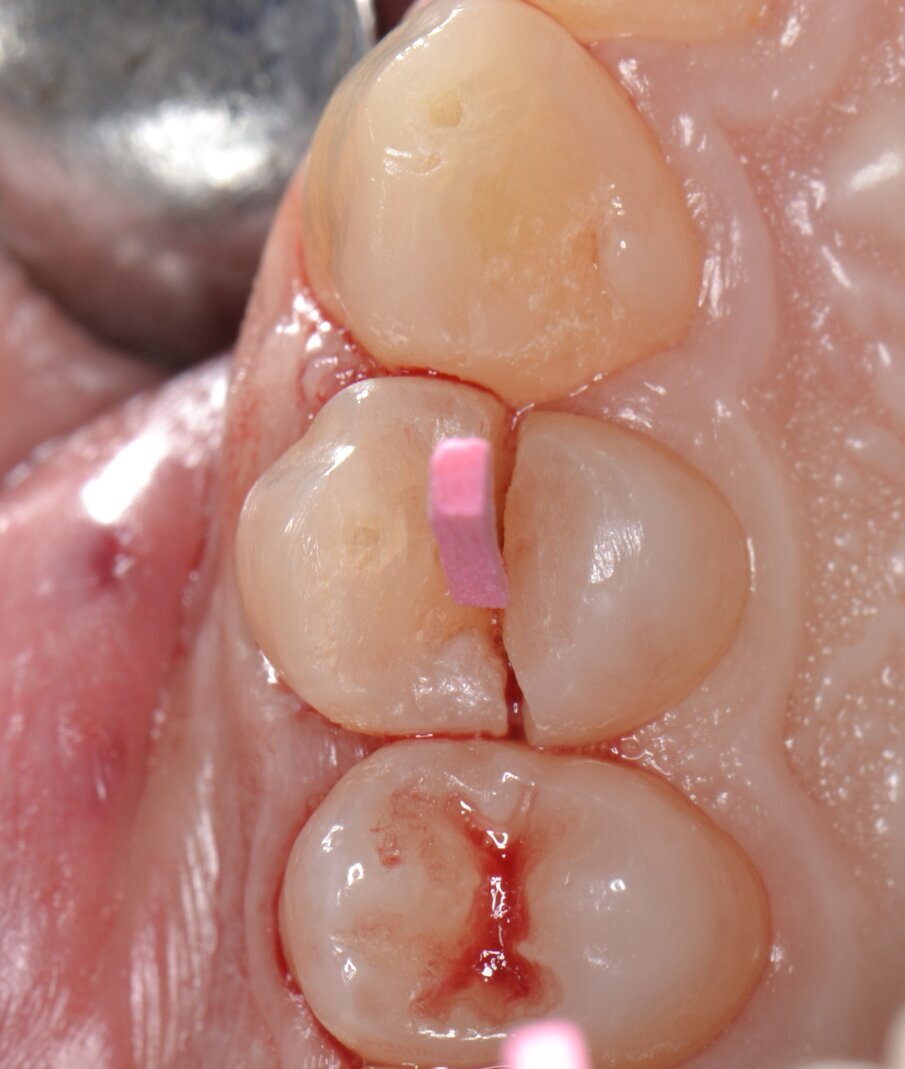

Successivamente, le due parti dell’elemento dentario vengono estratte separatamente avendo l’accortezza di usare estrema cautela nei movimenti di lussazione (Figg. 5, 6). Dopo aver completato la fase estrattiva (Fig. 7) ed aver controllato l’integrità delle pareti alveolari, il tunnel implantare viene preparato mediante l’utilizzo di inserti piezoelettrici dedicati (SUS – Surgery Ultrasonic Site, Esacrom Srl, Imola, Italia) (Fig. 8) con il duplice obiettivo di sfruttare il setto inter-radicolare per garantire una soddisfacente stabilità primaria e inserire l’impianto in posizione protesicamente guidata: una preparazione di tipo tradizionale con frese rotanti esporrebbe infatti al rischio di distruggere completamente il setto osseo che separa la radice buccale da quella palatale, costringendo l’operatore ad abortire la procedura o, in alternativa, a posizionare l’impianto in una delle due radici (Fig. 9).

Fig. 5 - Estrazione atraumatica dell’elemento 1.4.

Fig. 6 - Elemento 1.4 estratto.